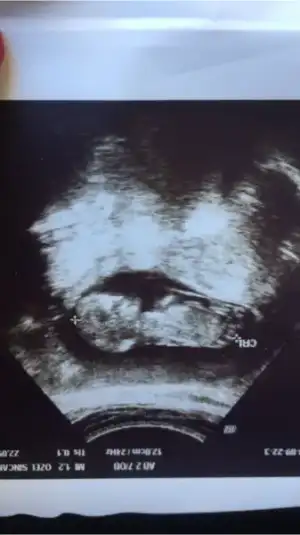

güzel günler diliyorum herkese :KK200: bugün sat a göre 11+0 da ultrasona göre 11+6 da ense kalınlı 1mm burun kemiği de oluşmuş çok şükür 51.4 mm boyumuz eller kollar bacaklar ayy Allah ım herkese yaşatsın bu duyguyu inşallah ikili test için kan da verdim 15 gün sonra çıkacakmış sonuç ben ultrasonda görünce tipinden kıza benzettim öyle geldi ama doktorun 16.haftadan önce cinsiyet tahmini yapmaya niyeti yok :KK12: özelin yolu göründü bize gene :21:

• 1B35BA12-8504-477D-AFE2-28C9CF5C5E6B.webp

1B35BA12-8504-477D-AFE2-28C9CF5C5E6B.webp

10 KB · Görüntüleme: 56

Evet canım erkek bende gördüm nuba göre çıkıntısı dikti:nazar: